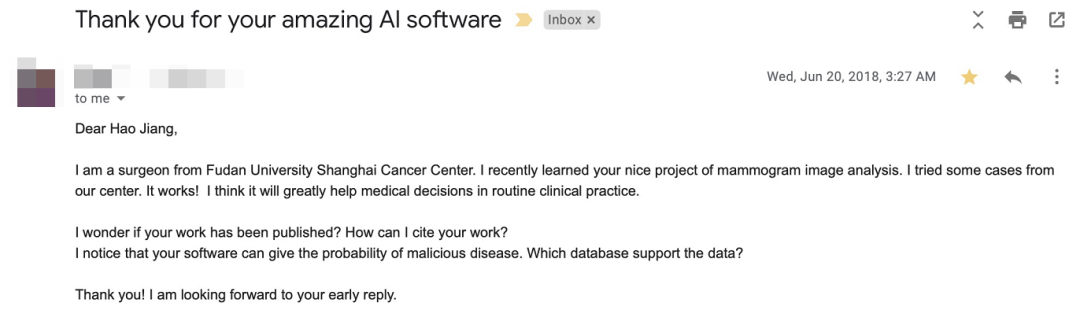

网站也因此获得了业内的广泛关注,期间不乏复旦大学外科等国内外医疗机构,用邮件的方式向他表达感谢,并愿意提供资金、技术支持。

毕竟,整件事 coolwulf 都是自费,这可不是一笔小数目。

复旦大学癌症中心发来的邮件 ▼